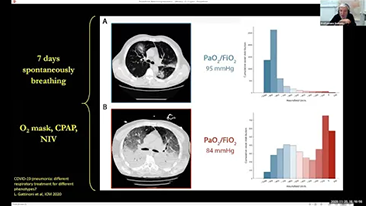

Das Beatmungsger?t im Einzelnen richtig einzustellen, ist bei der Behandlung von Patientinnen und Patienten mit Atemwegserkrankung von entscheidender Bedeutung . Da diese Einstellungen in Bezug auf s?mtliche Parameter von einem Arzt oder einer ?rztin vorgenommen werden, h?ngt ihre Angemessenheit direkt von deren Wissen und der Erfahrung, die sie mit solchen Einstellungen gesammelt haben, ab. In den letzten 20 Jahren hat sich der in der BeatmungsunterstĂŒtzung verfolgte Ansatz grundlegend weiterentwickelt. Ausgehend von den BedĂŒrfnissen der Praxis wurden zahlreiche Beatmungsmodi und Tools zur EntscheidungsunterstĂŒtzung entwickelt, die Zeit einzusparen und Fehler zu vermeiden helfen.